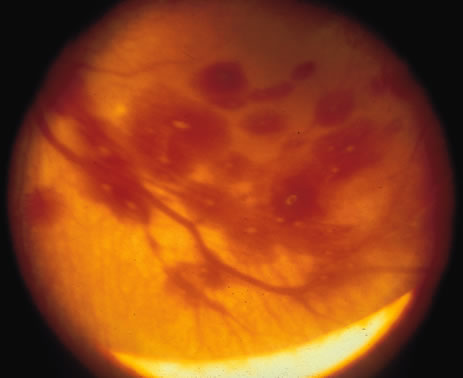

Retinal hemorrhage occurs with a reported frequency ranging from 2.6% to 50%.182,183 Intraretinal hemorrhages (flame-shaped, dot-blot, and larger dot-blot with white centers) are most commonly seen in the posterior pole but can be seen anteriorly (Fig. 8). Subhyaloid and subretinal hemorrhages occur much less frequently.

Fig. 8. Multiple round and white centered retinal hemorrhages in shaken baby syndrome.

A number of factors are likely responsible but birth trauma is the principal etiologic agent.183–185 Hemorrhages may result from compressive congestion of the vessels of the neck or from cavernous sinus congestion resulting from head compression. Therefore, they are more common in primiparas, with nuchal cords, or after delivery assisted by forceps or vacuum extraction. They are uncommon after cesarean section. Hypoxic vascular damage, neonatal vascular fragility, and various dysfunctions of coagulation (vitamin K, platelets, prothrombin) have also been implicated. These latter factors may be operative in premature neonates, who have a relatively high incidence of retinal hemorrhage.184 Vitamin E therapy for neonates may increase the incidence of these hemorrhages.186

Large round hemorrhages are more frequent after neck or head compression. The superficial flame-shaped type is more commonly associated with hypoxia but is often present without such a history. Subhyaloid hemorrhages may be associated with subarachnoid or subdural hemorrhage.187

Neonatal retinal hemorrhages often resolve within a few days to 3 weeks. One recent study documented that all neonatal retinal hemorrhages resolve by 4 weeks. Retinal hemorrhages in infants older than 4 weeks of age should suggest the possibility of other etiologies including nonaccidental trauma. A clinical work-up should be conducted to rule out serious central nervous system components of shaken baby syndrome and other evidence of abuse (rib and long bone fracture).188 Localized pigmentary changes may occur, but visual sequelae are exceedingly uncommon. The incidence of retinal hemorrhage has been correlated with central nervous system hemorrhage.186 No significant correlation between retinal hemorrhages and later cognitive development of the child has been noted, however.183